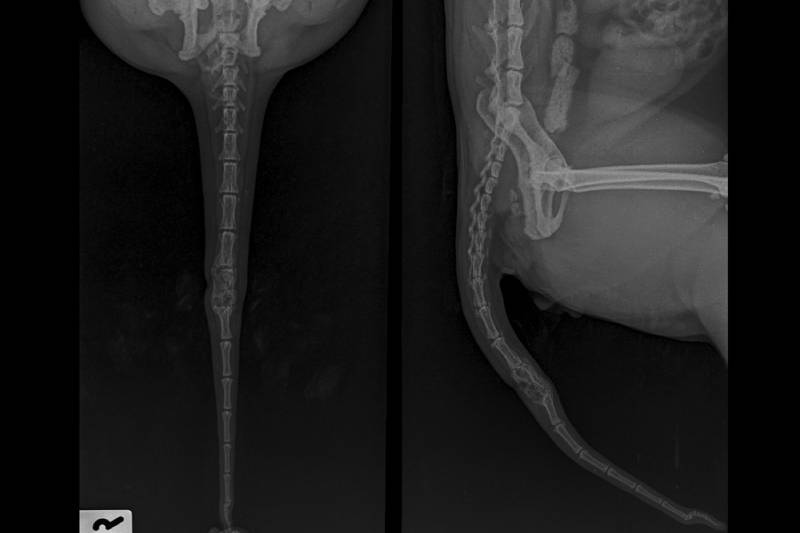

Degloved Cat Tail Injury Tail Bandage for Chronic Injury (NOT DIY, It